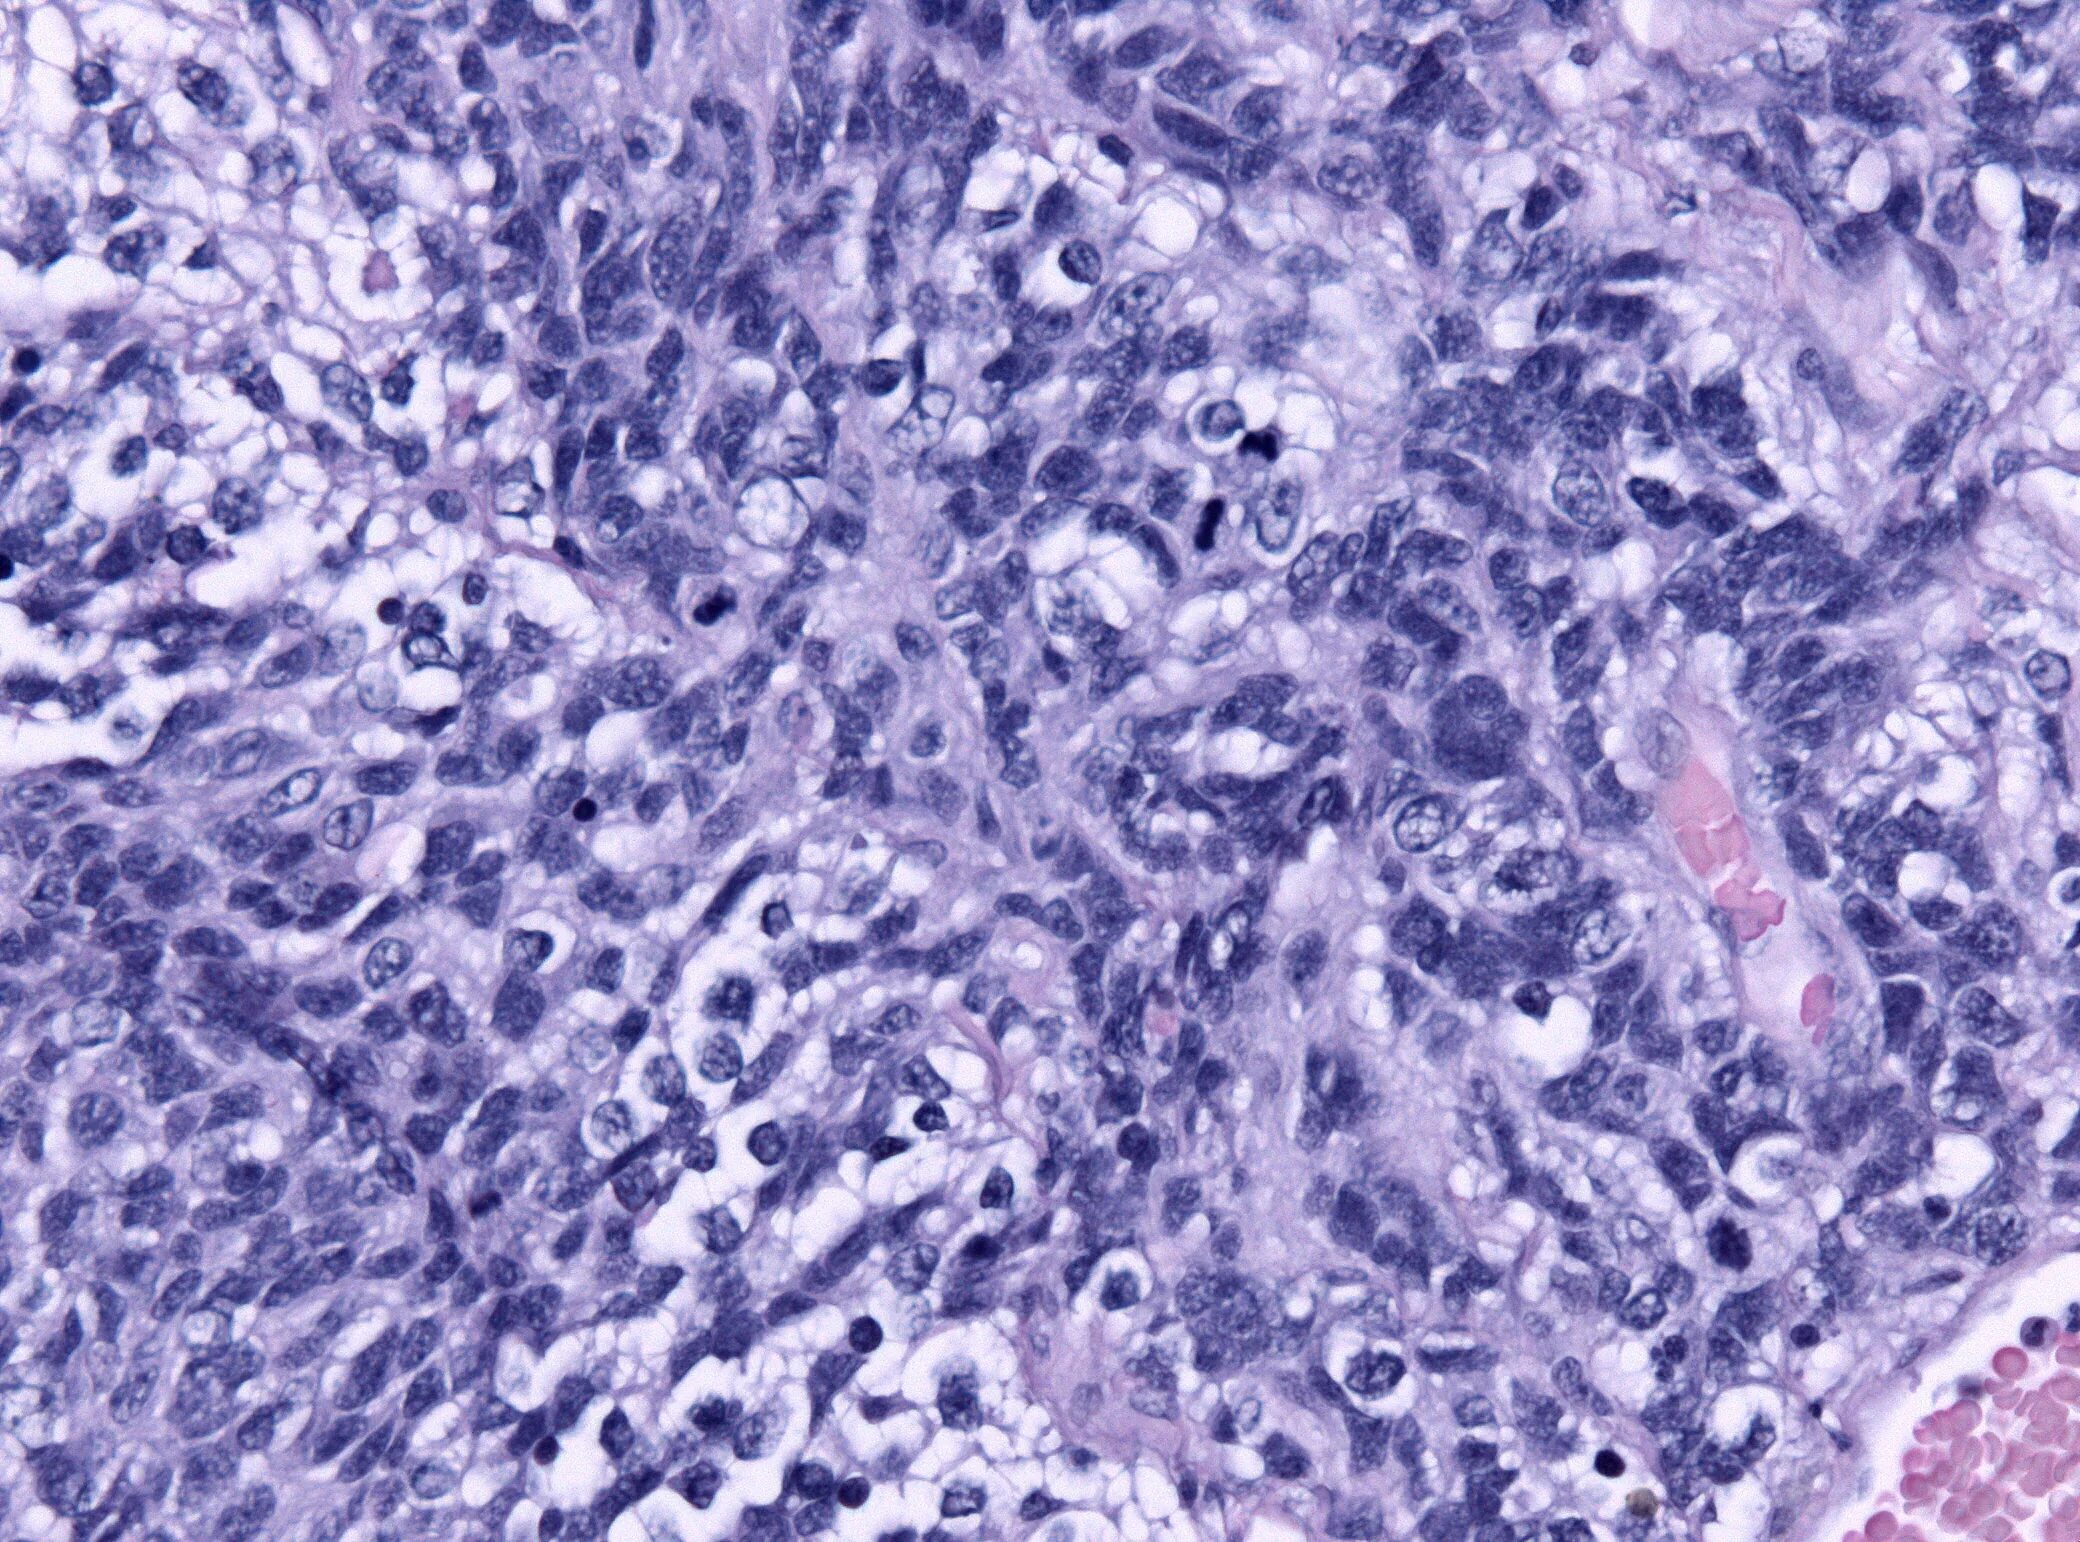

Медуллобластома это